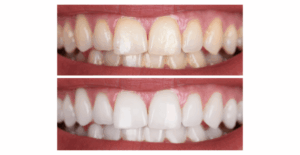

Dr. Elias Mansur | Há 21 anos transformando a vida das pessoas através da Implantodontia e Ortodontia em Ponta Grossa - PR. Todos os direitos reservados